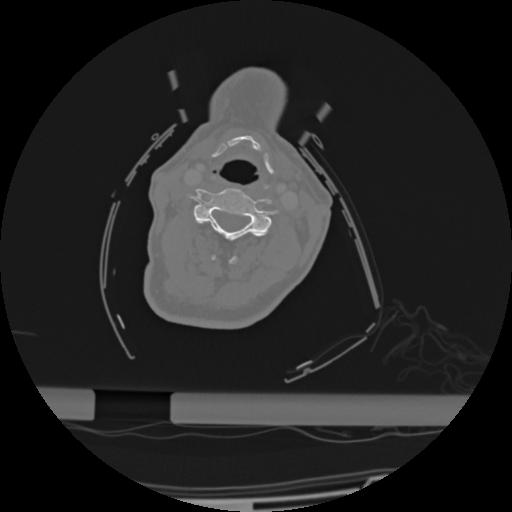

22 ANGIO,CE,Vol,0.5,ANGIO,,